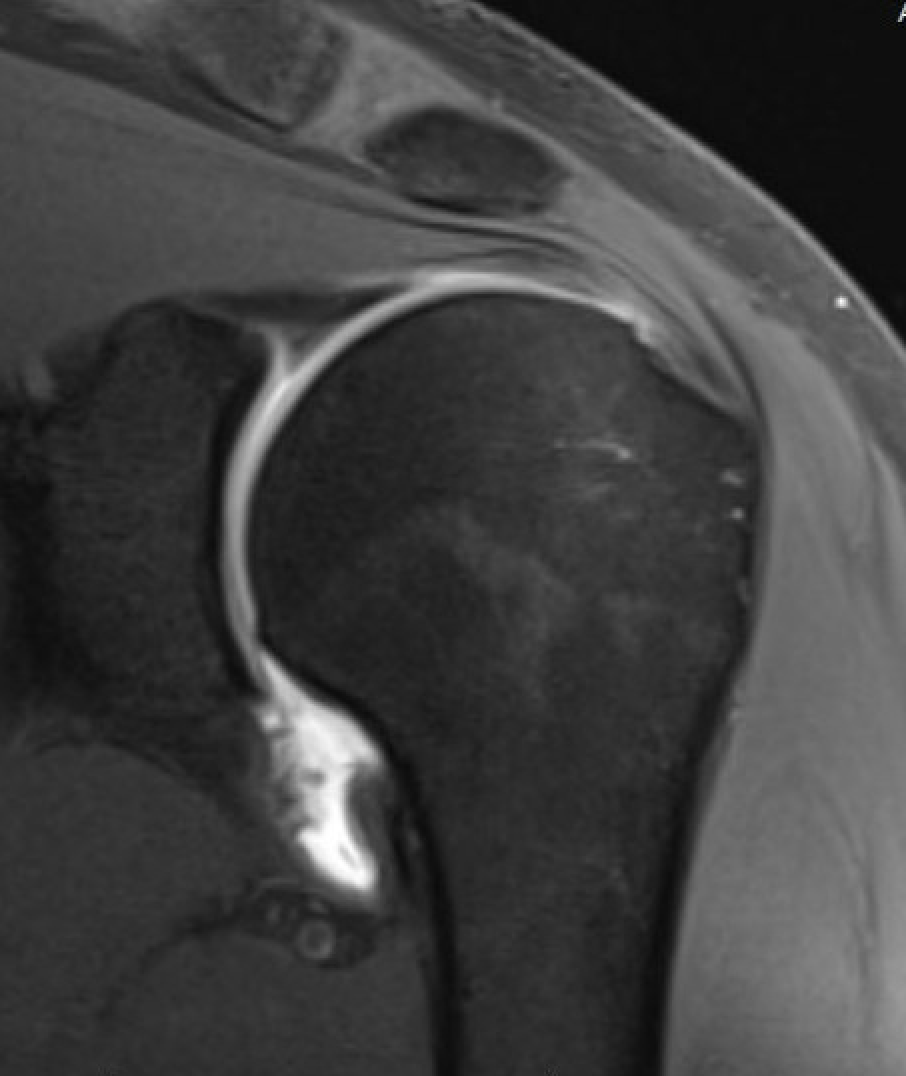

MRI

Normal HAGL / J Sign

U shaped appearance

Normal IGHL insertion on the humeral neck

J shaped

Avulsion of the IGHL

MRI Normal IGHL HAGL MRI